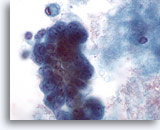

Figure 28: Breast FNA, Ductal carcinoma in situ. This is a cellular aspirate showing clusters of tumor cells, single malignant cells and foamy macrophages. Ductal carcinoma in situ (DCIS) often shows myoepithelial cells overlying the malignant cell clusters. Tumor cells tend to be clustered rather than single as in invasive tumor. In addition, tubular structures are not associated with DCIS. Comedo DCIS is characteristically associated with necrosis and calcium. 40x

Figure 28

Breast FNA, Ductal carcinoma in situ.

This is a cellular aspirate showing clusters of tumor cells, single malignant cells and foamy macrophages. Ductal carcinoma in situ (DCIS) often shows myoepithelial cells overlying the malignant cell clusters. Tumor cells tend to be clustered rather than single as in invasive tumor. In addition, tubular structures are not associated with DCIS. Comedo DCIS is characteristically associated with necrosis and calcium.

40x